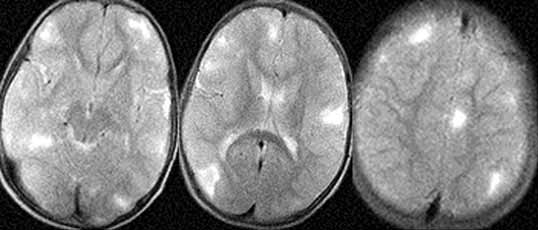

Туберозный склероз.

Рис. 2. МР-томограммы головного мозга, Т2-взвешенные изображения. Выявляются множественные очаги гиперинтенсивные в Т2W.